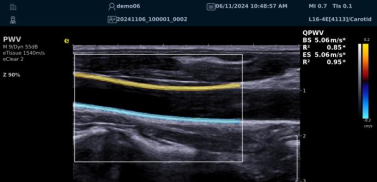

QPWV 彩色脉搏波传导速度定量技术

QPWV 技术是百乐博平台医疗的极速脉搏波速度测量技术,对脑卒中诊疗优势明显:

image.png

? 可进行动脉壁运动速度 - 时间彩色成像,直接测量单点脉搏波传导速度及相关参数(如 BSES 时的速度及标准差)。

? 能在血管内中膜增厚前的内皮功能不全阶段检测异常,对早期动脉硬化评估极具临床价值。

? 操作简单直接,无需附加设备,影响因素少,检测快速、重复性和稳定性高。